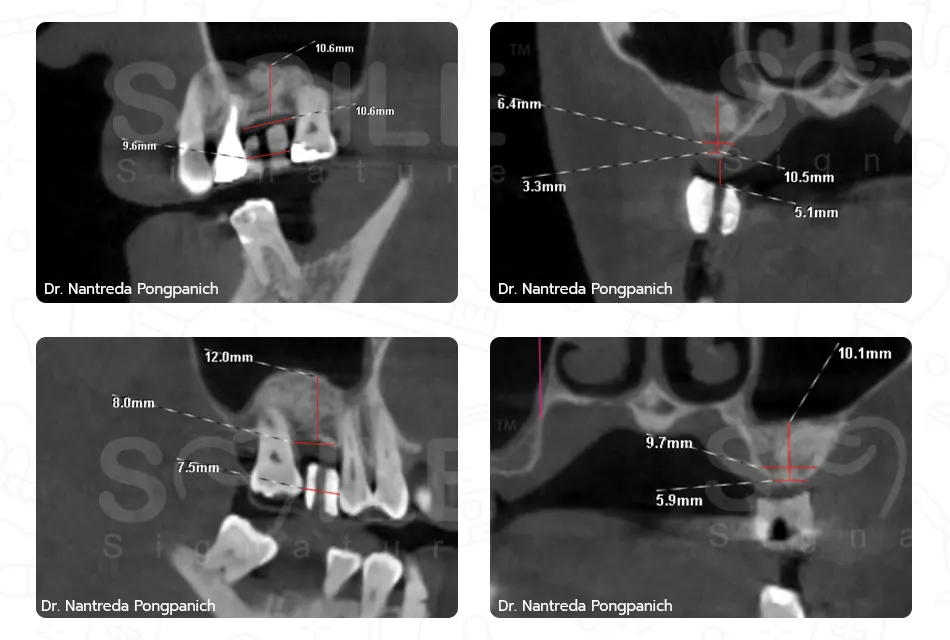

Image Box text